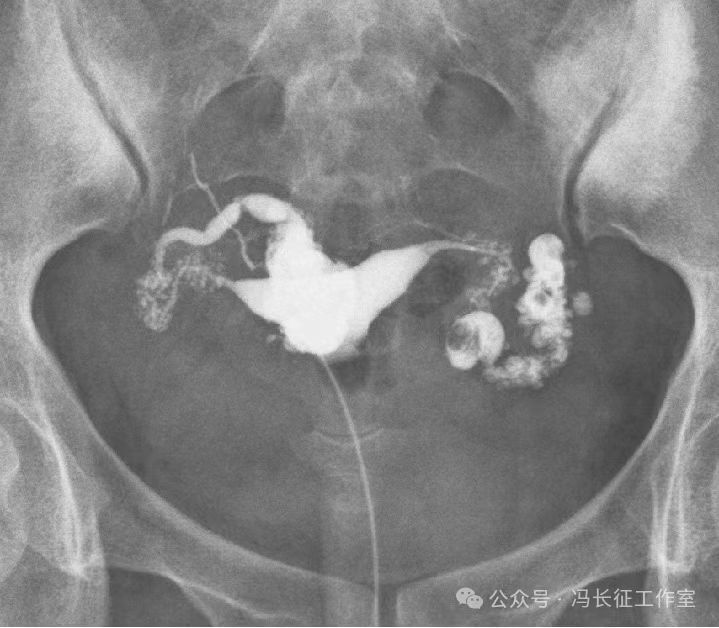

输卵管积水的子宫输卵管造影尽量包括这5个方面的描述,诊断的临床意义才最大,这样才能给好的生殖科医生有价值的建议,帮助给不孕者制定最好的助孕治疗方案。比如这例输卵管积水,峡部结节性输卵管炎(病因),交通性(积水近端是否和宫腔相通),中度(积水大小),厚壁(管壁的厚度),多囊(囊腔的多少)。

微信图片_20240220111146(3).jpg

最后诊断应该是:双侧峡部结节性输卵管炎并双侧中度、厚壁、多囊、交通性输卵管积水。